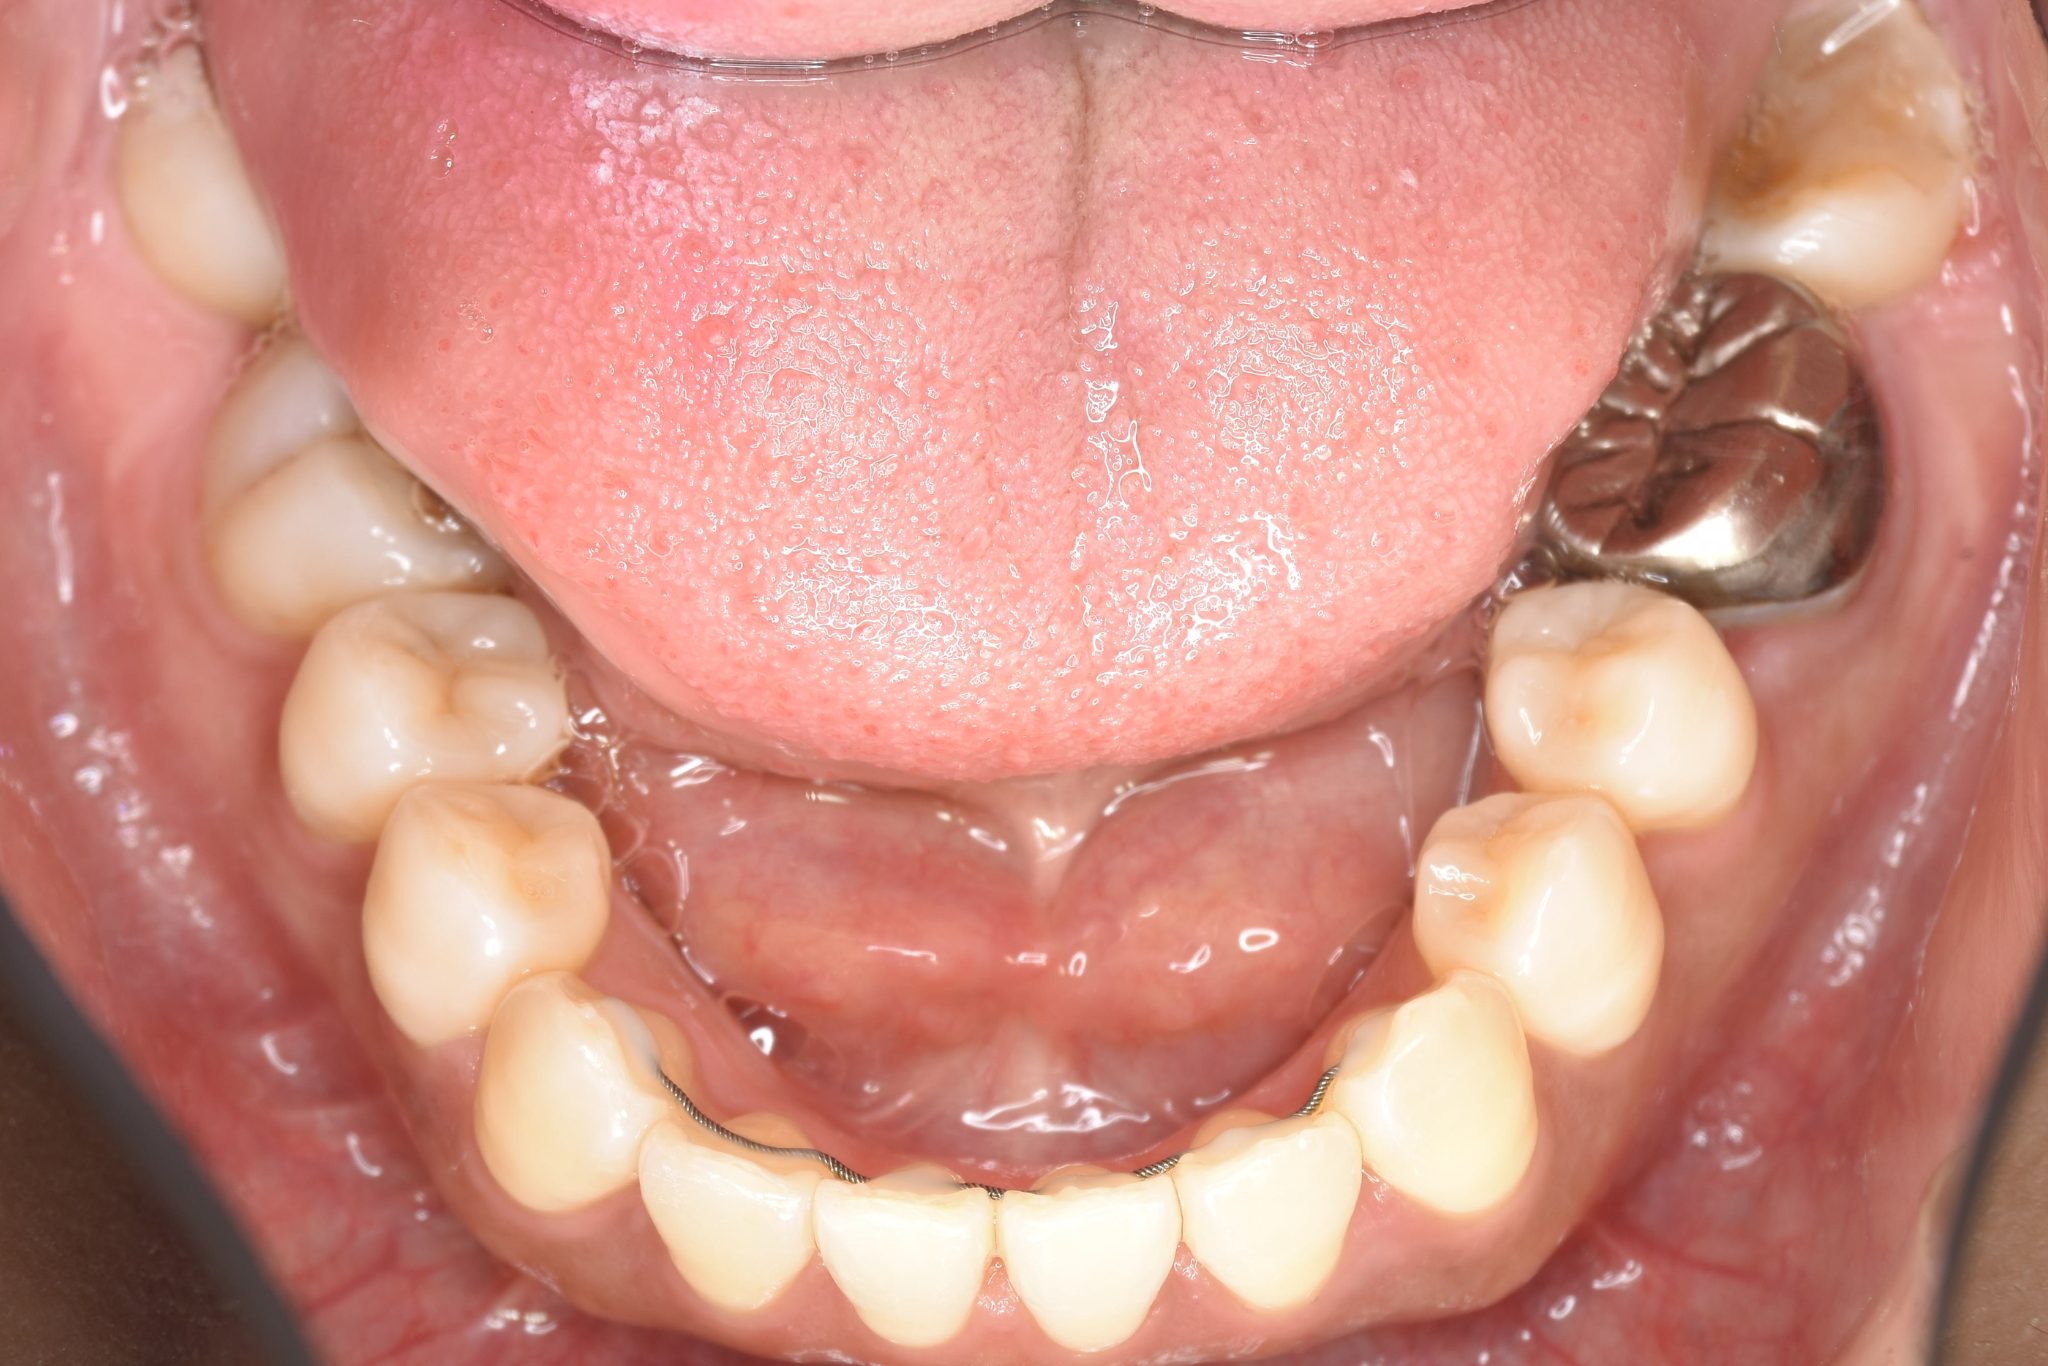

アフター

全顎ワイヤー矯正 症例_141